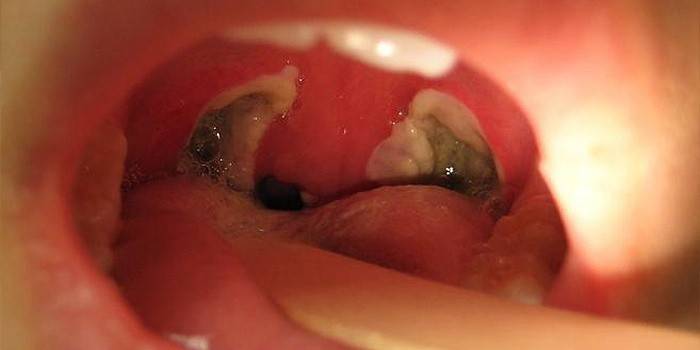

Plugues de amigdalite

O pus nas amígdalas tem uma aparência característica: manchas esbranquiçadas arredondadas, levemente salientes. Companheiros frequentes de amigdalite crônica são lacunas cheias de pus. Vendo uma foto de cortiça purulenta, não é difícil reconhecer tal quadro em sua própria garganta. As partes restantes da garganta parecem saudáveis, às vezes há vermelhidão dos arcos palatinos. Plugues profundamente localizados levam ao crescimento excessivo das lacunas, o pus se espalha na fibra e os abscessos podem se formar.